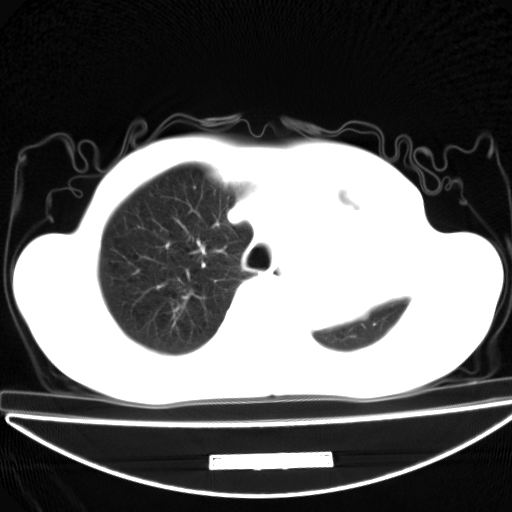

以下是引用杀毒软件在2009-4-28 17:58:00的发言:[br]考虑----左肺慢性肺脓肿形成继发上叶含气不良---抗炎后复查---待排肿瘤所致[br][br][本贴已被 杀毒软件 于 2009-4-28 18:01:26 修改过]